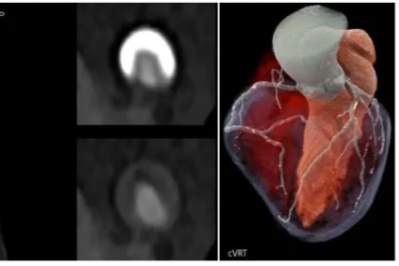

不开胸换「心门」!绵阳市中心医院心血管内科完成川西北地区首两例微创瓣膜置换